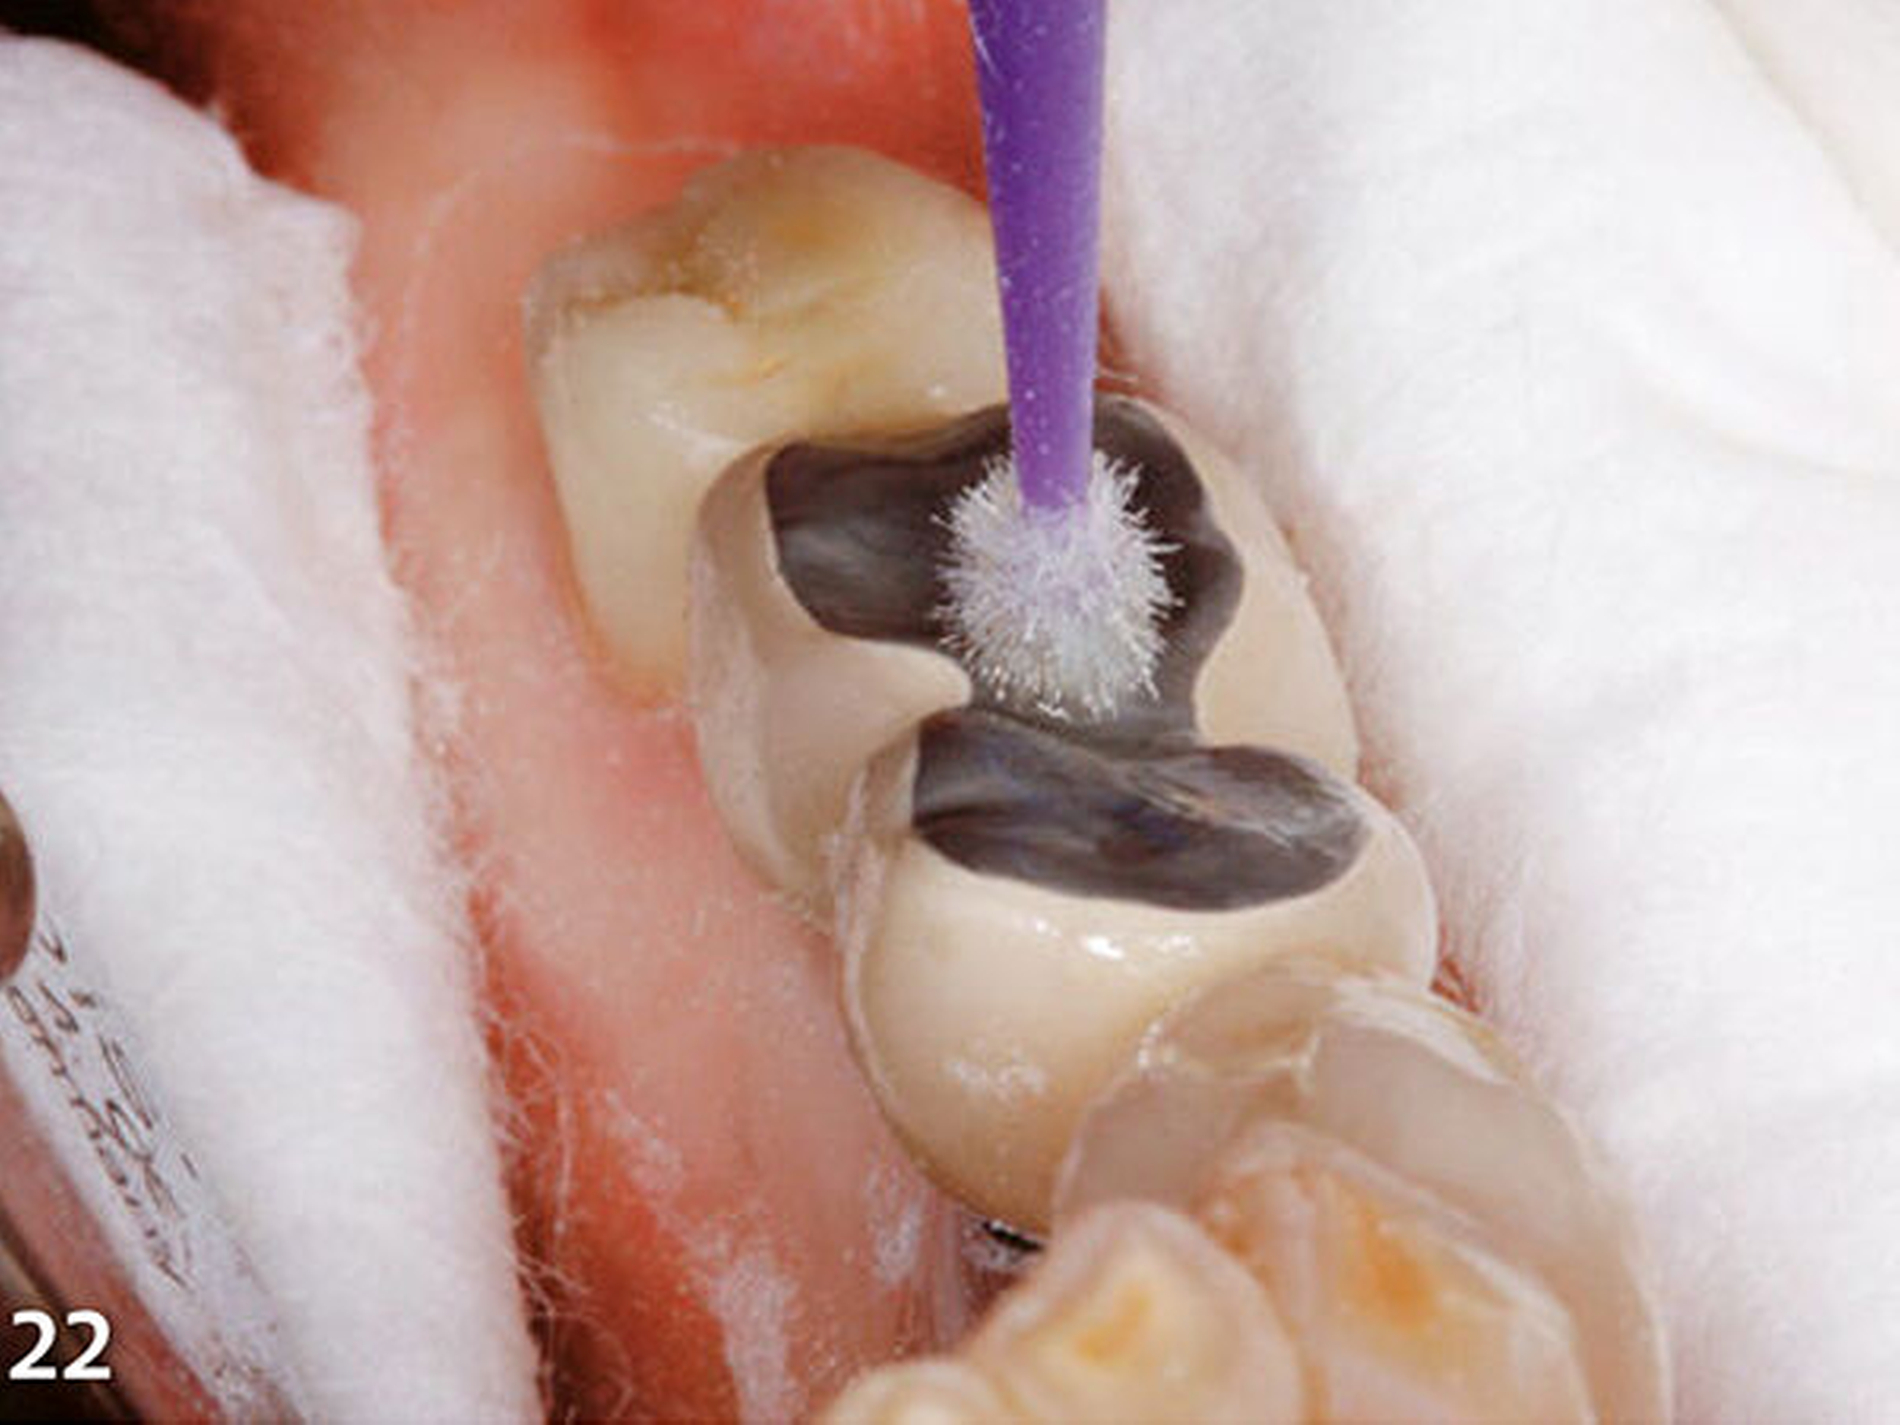

In korrekter Endposition stellt die Schiene die verloren gegangene Zahnhartsubstanz als Hohlraum zwischen Schienenkunststoff und okklusalen Restzahnanteilen dar (Schmidlin et al. 2009c). Nachdem die Schiene zum Schutz der Weichgewebe, an der selektiv die vorzubehandelnden Bereiche freigeschnitten wurden, intraoral positioniert wurde (Abb.20), erfolgte mit einem intraoralen Sandstrahlgerät die tribochemische Silikatisierung (CoJet, 3M Espe) im Bereich der okklusalen Oberflächen der vorhandenen Restaurationen (Abb.21) (Frankenberger et al. 2000, 2014; Matinlinna 2013; Ozcan 2003). Nach Entnahme der Schutzschiene wurde auf die derart silikatisierten Oberflächen sorgfältig ein Silan aufgetragen (Abb.22) (Blatz et al. 2003; Kupiec et al. 1996).

Diese beiden Schritte dienen zum Aufbau einer chemischen Verbindung zwischen den alten Kauflächen aus Metall bzw. Keramik und den nachfolgend einzubringenden neuen Aufbauten aus Komposit. In Vorbereitung zur Applikation des Komposits wurden nachfolgend die silanisierten Oberflächen mit einem Adhäsiv benetzt, welches dünn verblasen und sofort mit Licht polymerisiert wurde. Wenn eine kontaminationsfreie Arbeitsumgebung durch relative Trockenlegung mittels Watterollen bzw. Wangenkissen und effektiver Absaug- bzw. Abhaltetechnik durch eine erfahrene zahnmedizinische Fachassistenz sichergestellt ist, kann bei Adhäsivrestaurationen auf eine absolute Trockenlegung mit Kofferdam verzichtet werden (Brunthaler et al. 2003; Heintze et al. 2015; Opdam et al. 2016; Raskin et al. 2000; Smales 1993; van Dijken & Horstedt 1987).